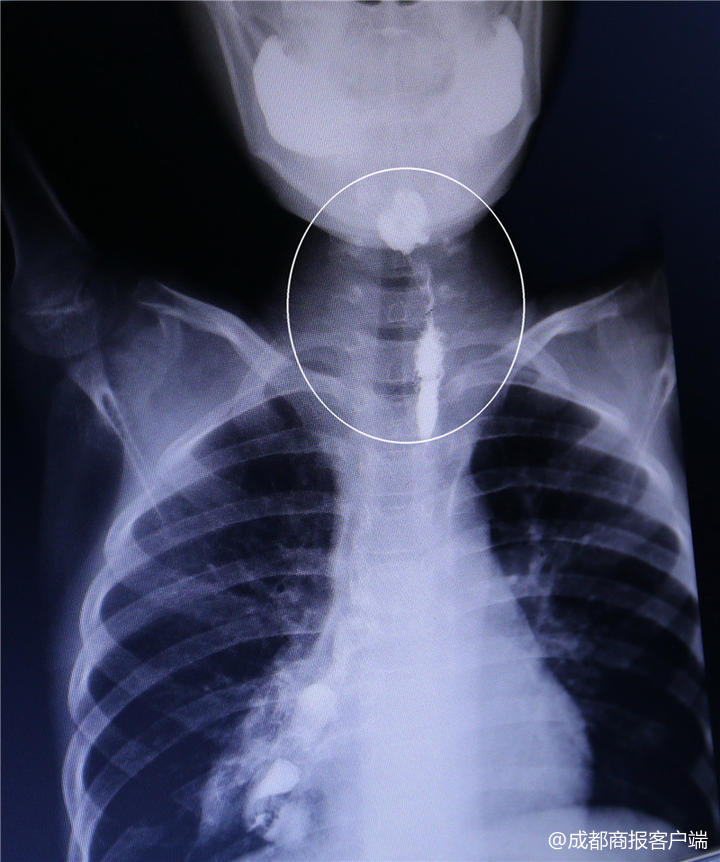

“挛缩的部位在第4颈椎和第7颈椎位置之间,大约有5厘米长。”赵虎介绍说,检查结果发现,琳琳结肠再造的食道挛缩严重,进食通道十分狭窄,最窄的位置只有1.8毫米。

“我们的扩张球囊,常规的是直径2.5毫米。”赵虎说,世界上最细的食道扩张球囊都有2毫米,但是因为是实心的,很硬,无法进入狭窄的食道。反复地尝试发现,常规的扩张设备无法成功,赵虎想起了婴儿用的胃管,“先试了8号胃管,直径还是有2.6毫米。”赵虎又找来了用于新生儿治疗的6号胃管,直径为2毫米,但因为胃管比较柔软,适应性比较强。

赵虎尝试着,用介入科最细的、仅有0.9号的泥鳅导丝,在影像引导下,探入了狭窄的食道,进入胃部,“只有导丝进去了,没有用,不能完成扩张。”赵虎说,随后,他又将新生儿胃管通过导丝引导,慢慢地放进了食道,抵达胃部。